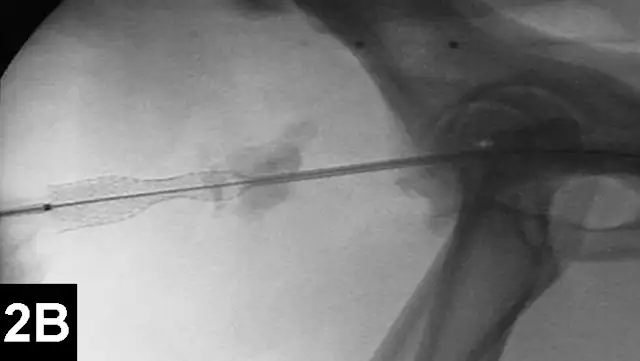

In IR, the goal for intrahepatic portosystemic shunts is to reduce the perioperative mortality rates associated with traditional open surgery and to improve outcomes (Figure 3). The author has recently reported 100 cases of intrahepatic portosystemic shunts in dogs that have been managed using IR techniques. Perioperative mortality rates were approximately 3%, and other complications were minor. The majority of these dogs have continued to do well following prolonged follow-up times.12

Figure 3A: Serial fluoroscopic images in a dog with a left divisional intrahepatic shunt.

The dog is in dorsal recumbency with the head to the left.

Double venogram of caudal vena cava (CVC) and portosystemic shunt (PSS) demonstrating entrance of shunt (*) into CVC.